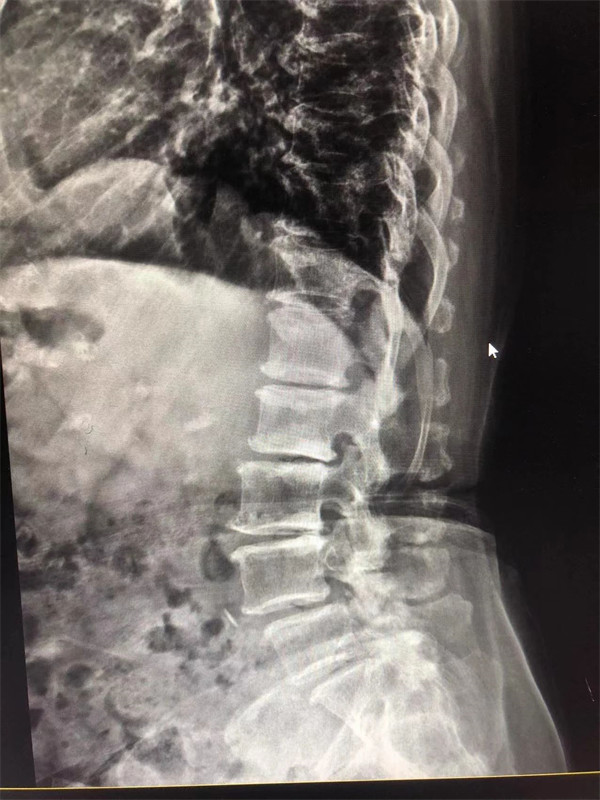

手術前↓

戈主任仔細詢問阿婆病情癥狀,綜合查體及MRI片情況,認為阿婆有明顯的腰椎滑脫,腰椎管狹窄,這是引發(fā)阿婆病痛的主要因素。

阿婆曾在院外多家醫(yī)院就醫(yī),被診斷為腰4椎體滑脫癥、腰椎管狹窄癥、腰椎間盤突出癥,外院予以止痛、理療、針灸等各種保守方式治療,病情未見明顯改善。